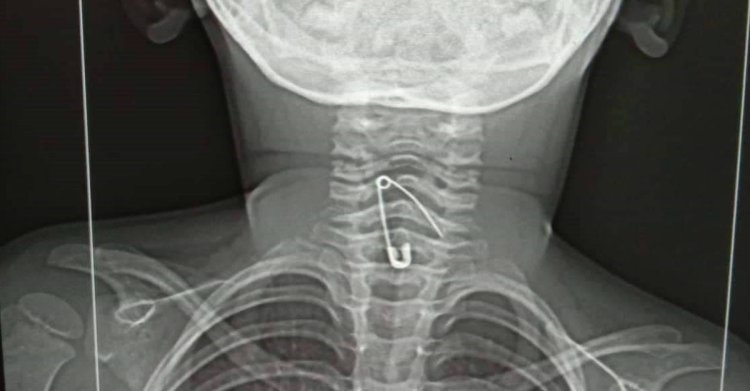

প্রথম নিউজ রাজশাহী: মায়ের হাতে নুডলস খেতে গিয়ে সোহানা আক্তার জিদনি (৩) নামে এক শিশুর গলায় সেফটি পিন আটকে গেছে। অসুস্থ অবস্থায় বৃহস্পতিবার (২৫ আগস্ট) দিবাগত রাত ১২টার দিকে তাকে রাজশাহী মেডিকেল কলেজ (রামেক) হাসপাতালে নেওয়া হয়েছে।

হাসপাতালে শিশুটির সঙ্গে এসেছেন তার চাচাতো ভাই হাসান আলী। তিনি বলেন, বৃহস্পতিবার বিকেলের দিকে শিশু জিদনিকে নুডলস খাওয়াচ্ছিলেন তার মা জুলেখা বেগম। একপর্যায়ে তার গলায় কিছু একটা আটকে যায়। এরপর শিশুটি বমি করতে করতে অসুস্থ হয়ে পড়ে। রাতেই তাকে রাজশাহীর বাঘা উপজেলার একটি ক্লিনিকে নেওয়া হয়। এক্স-রে করে সেখানে গলায় সেফটি পিন আটকে থাকতে দেখা যায়। সেখান থেকে রাত ১২টার দিকে জিদনিকে রামেক হাসপাতালে আনা হয়েছে।

শুক্রবার (২৬ আগস্ট) সকাল ৮টার দিকে রাজশাহীর ইসলামী ব্যাংক মেডিকেল কলেজ হাসপাতালে ফের এক্স-রে করা হয়েছে। সেখানেও গলায় সেফটি পিন আটকে থাকতে দেখা গেছে। হাসান আলী আরও জানান, কীভাবে গলায় সেফটি পিন গেল সেটি বোঝা যাচ্ছে না। সেফটি পিন পানিতে ছিল, নাকি নুডলসের মধ্যে ছিল তা নিশ্চিত হওয়া যায়নি।